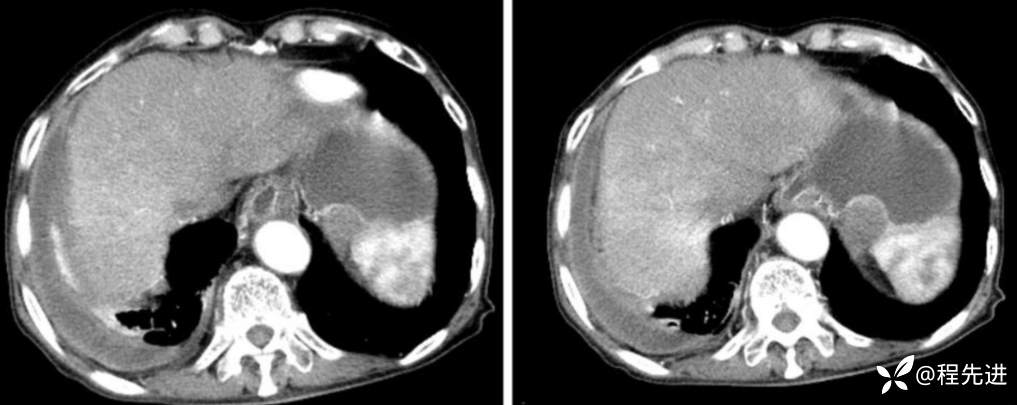

CT

平扫

动脉期